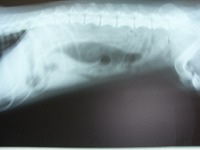

もう1件(成犬)は、飲み込んだ現場を確認できたわけではなく、嘔吐症状が強いので、検査のためにレントゲンを撮って判明したものです。

レントゲン写真からでは、飲み込んだものが何であるかまでは分かりませんでしたが、嘔吐症状、大きさ、レントゲン写真上の存在位置から緊急手術が必要と判断し、開腹手術をして取り出すことになりました。

お腹を開けると、十二指腸の部分が完全に詰まっていて瘤のように腫れ、ひどく充血していました。

十二指腸を切開し、出て来たもの(飲み込んだもの)は消しゴムです。消しゴムは変質して石のようにカチカチになっていましたので、飲み込んでから長期(数ヶ月あるいは数年以上)にわたり胃内に存在したものと思われます。消化することも、吐くことも出来ないまま胃内に留まり、その後、何らかのきっかけで胃から腸へ運ばれて、十二指腸の部分で栓塞し、腸管組織に決定的なダメージを与える寸前だったのです。十二指腸には胆汁・膵液を分泌する管が開口していますので、デリケートな重要な場所です。結果的には、無事回復しましたが、本当に危ないところでした。以上の他にも、焼き鳥を串ごと丸呑みし、竹串が胃壁を突き破ったケース、硬貨、ボタン、カーペットの端、ぬいぐるみの中身(スポンジ)、小石、桃の種、縫い針(咽喉の奥に刺さっていました)、などなど、誤嚥事故で来院するワンコは毎年発生しています。好奇心いっぱいで手当たり次第、何でも口に入れたがる子犬、食いしん坊ワンコの飼い主の皆様には、以下のことをぜひ徹底ください。